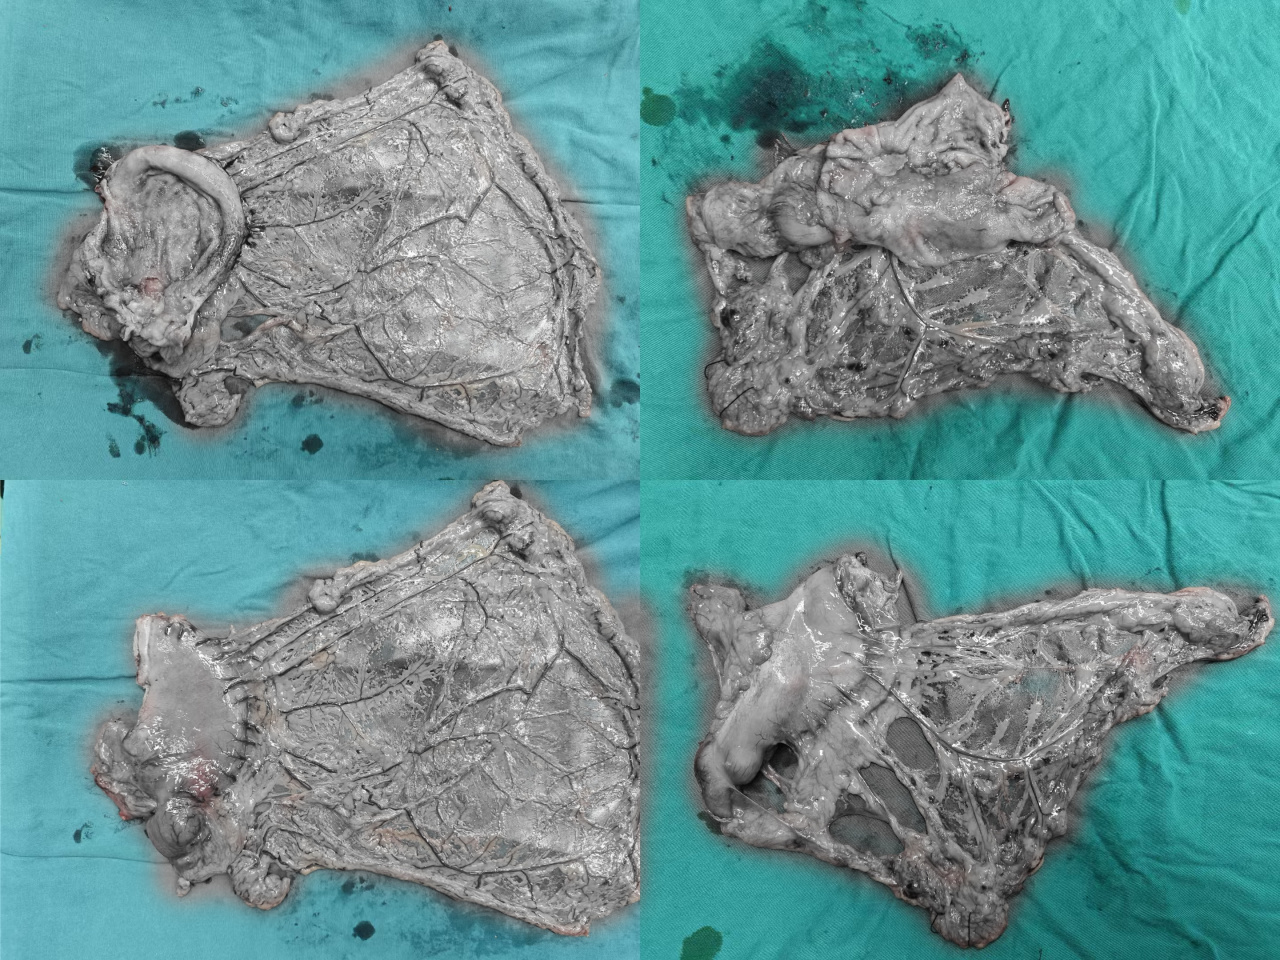

照片已部分黑白化处理,点击仍需谨慎

标准的胃癌根治术